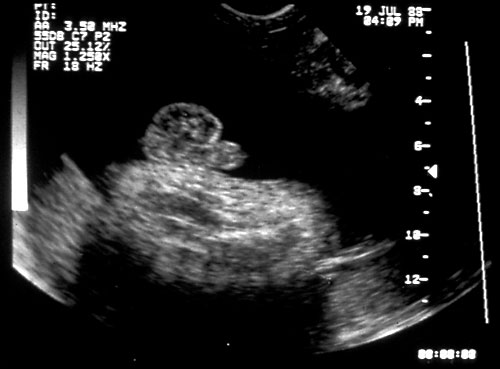

- Diaphragms — visualize in sagittal plane.

Normal diaphragm seen below right lung and above the liver in the middle of the picture with the hepatic veins diving below diaphragm. - Abdominal circumference.